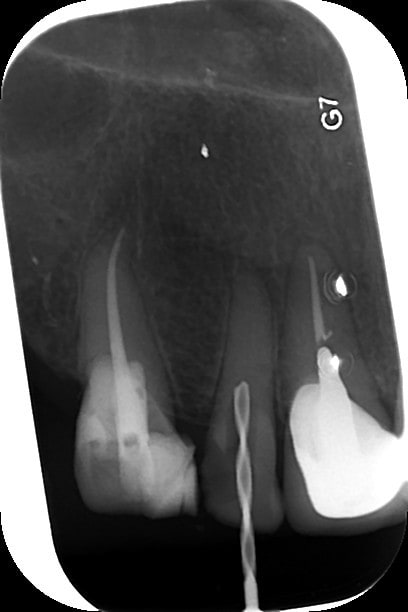

Cette semaine, j'ai galéré deux séances de 30 min pour traiter une incisive latérale maxillaire complètement calcifiée... J'ai essayé le forêt pilote, puis j'y suis allé carrément à la fraise diamentée fine pour rejoindre une portion de canal non oblitérée plus apicalement...

Quid du traitement d'une molaire nécrosée et complètement calcifiée?

http://www.endoexperience.com/pro_newsMar02.html

http://www.theendoblog.com/2007/12/finding-calcified-canal.html